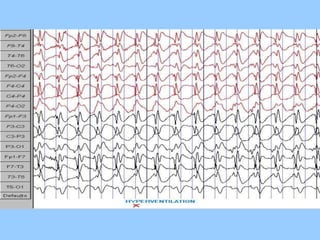

1. The document discusses EEG patterns and findings in various neurological conditions seen in children. It includes descriptions of normal EEG findings as well as abnormal patterns seen in conditions like absence seizures, West syndrome, benign childhood epilepsy with centrotemporal spikes, Lennox-Gastaut syndrome, non-convulsive status epilepticus, subacute sclerosing panencephalitis, and herpes encephalitis.

2. Case studies are presented with clinical histories and EEG findings to illustrate different pathologies. Treatment options are also mentioned for many of the conditions.

3. International standards for EEG electrode placement and recording parameters are reviewed. Characteristics of different EEG waves, amplitudes, and patterns are described.